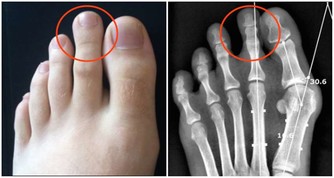

一、敲膽經:活血排毒、排水腫

按摩敲打膽經,可以舒經通絡、活血排毒,血液循環快了,身體就會有足夠的能量來排除垃圾,體內的水腫、毒素自然就會去除,按摩敲打的部位就會瘦下去。

膽經在下肢的巡行路線是沿股、下肢外側中線下行至小趾、次趾之間。有個很容易找到的標誌,就是沿著褲子中間的那條線至膝蓋側面處,主要是環跳、風市、中瀆、膝陽關四個穴位。